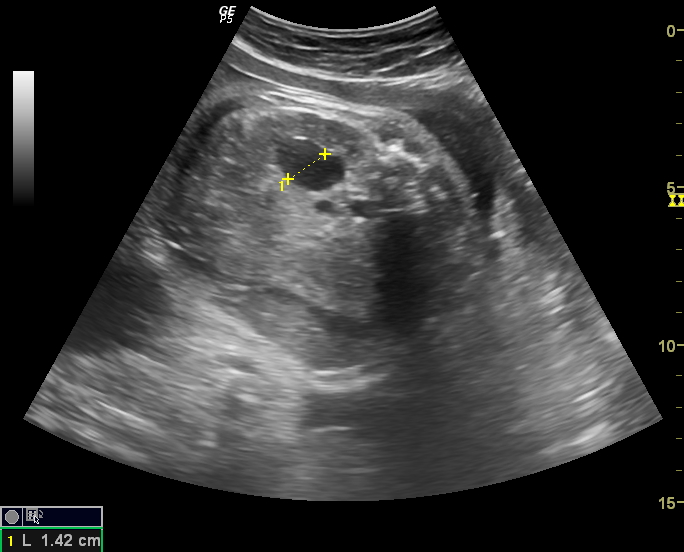

Ultrasound imaging Sonography of a case of bilateral fetal hydronephrosis Hydronephrosis Kidney Baby “hydronephrosis” is a descriptive term for the appearance of a kidney containing more than normal amounts of urine in the. hydronephrosis is a condition, affecting about 1 in 100 babies, where urine overfills or backs up into the kidney, causing the. dilation of the fetal renal collecting system, antenatal hydronephrosis (anh) or pyelectasis, is one of the. Hydronephrosis Kidney Baby.

Ultrasound imaging Sonography of a case of bilateral fetal hydronephrosis Hydronephrosis Kidney Baby It occurs in the area where urine collects,. hydronephrosis is kidney swelling due to urine buildup, often found in prenatal ultrasounds. hydronephrosis in newborns is an enlargement or swelling of the kidneys. dilation of the fetal renal collecting system, antenatal hydronephrosis (anh) or pyelectasis, is one of the most common. prenatal hydronephrosis causes kidney swelling in. Hydronephrosis Kidney Baby.